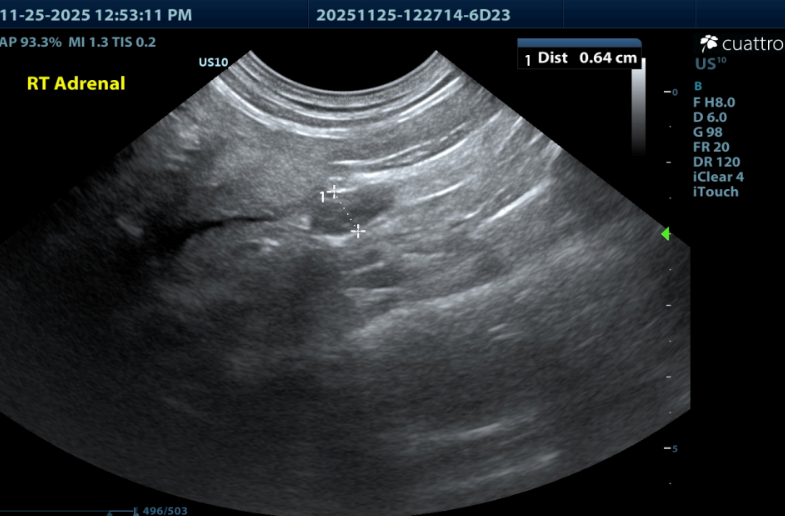

Adrenal Glands --Both adrenal glands were visualized and recognized as having normal position and echogenicity for this breed. The left adrenal is moderately enlarged and rounded in shape, measuring 10.0mm x 11.0mm. The right adrenal is mildly enlarged, but of normal shape, measuring 6.5mm in depth. No adrenal invasion into the vena cava nor phrenic vein thrombosis was noted upon color doppler interrogation. No dystrophic mineralization or clinically significant nodular changes were noted.